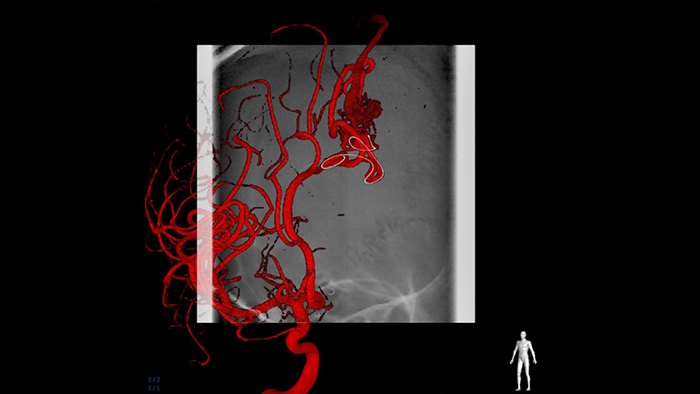

複雑な血管構造を3Dで可視化

SmartCT Angioは、数秒で3D再構成画像を表示させ、feeding arteries, draining veins , arterialized veins, nidus 、破裂、未破裂の評価を支援して意思決定をサポートします。3D画像は高い分解能で可視化され、重要な細部の視認性を高めるための自動体動補正機能を有しています。